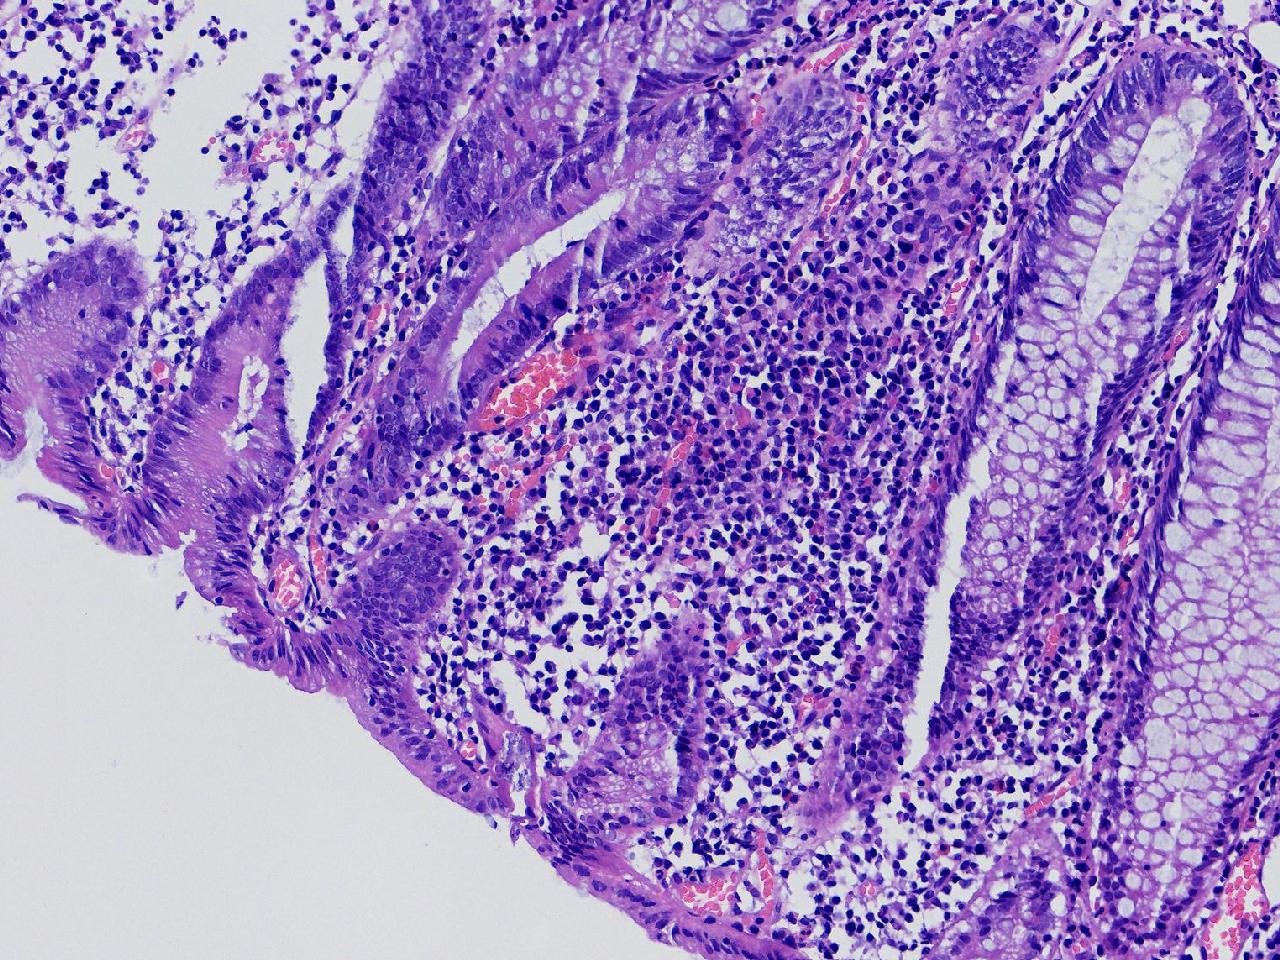

男,62岁,直肠见一直径约0.8cm大小的扁平隆起,表面光滑,活检1块。

直肠活检

灰白色不整形软组织1块,直径0.2厘米。

隐窝脓肿,杯状细胞减少,溃结考虑吗

炎症性肠病,溃结可能

不除外炎症性肠病,结合临床。